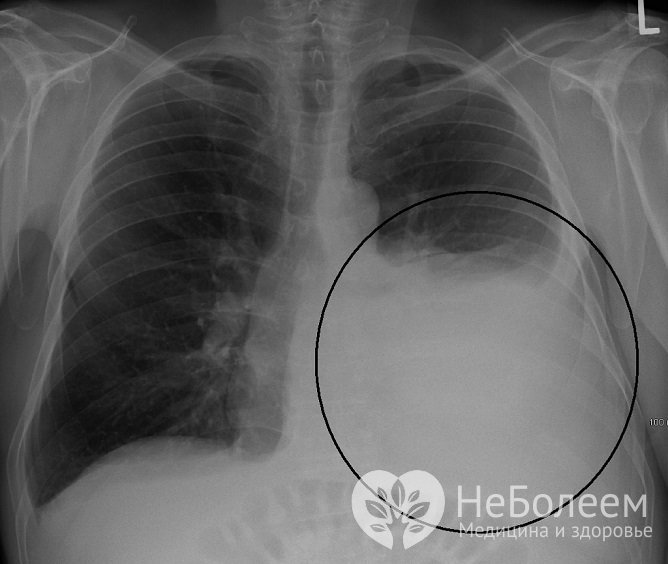

Гидроторакс на рентгеновском снимкеТакие лабораторные методы исследования, как общий анализ крови и мочи, биохимический анализ крови диагностической ценности для подтверждения гидроторакса не имеют. С целью дифференциальной диагностики характера жидкости (транссудат, экссудат) осуществляется проба Ривальты, позволяющая подтвердить или опровергнуть воспалительный характер содержимого гидроторакса.